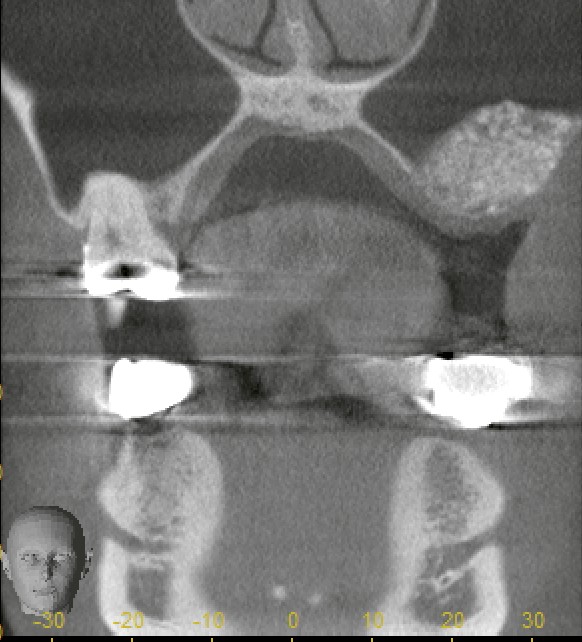

「サイナスリフト(ラテラルアプローチ)後。上顎奥歯部のインプラントに必要な骨量を確保するため、上顎洞粘膜を丁寧に挙上し骨造成を行っています。」